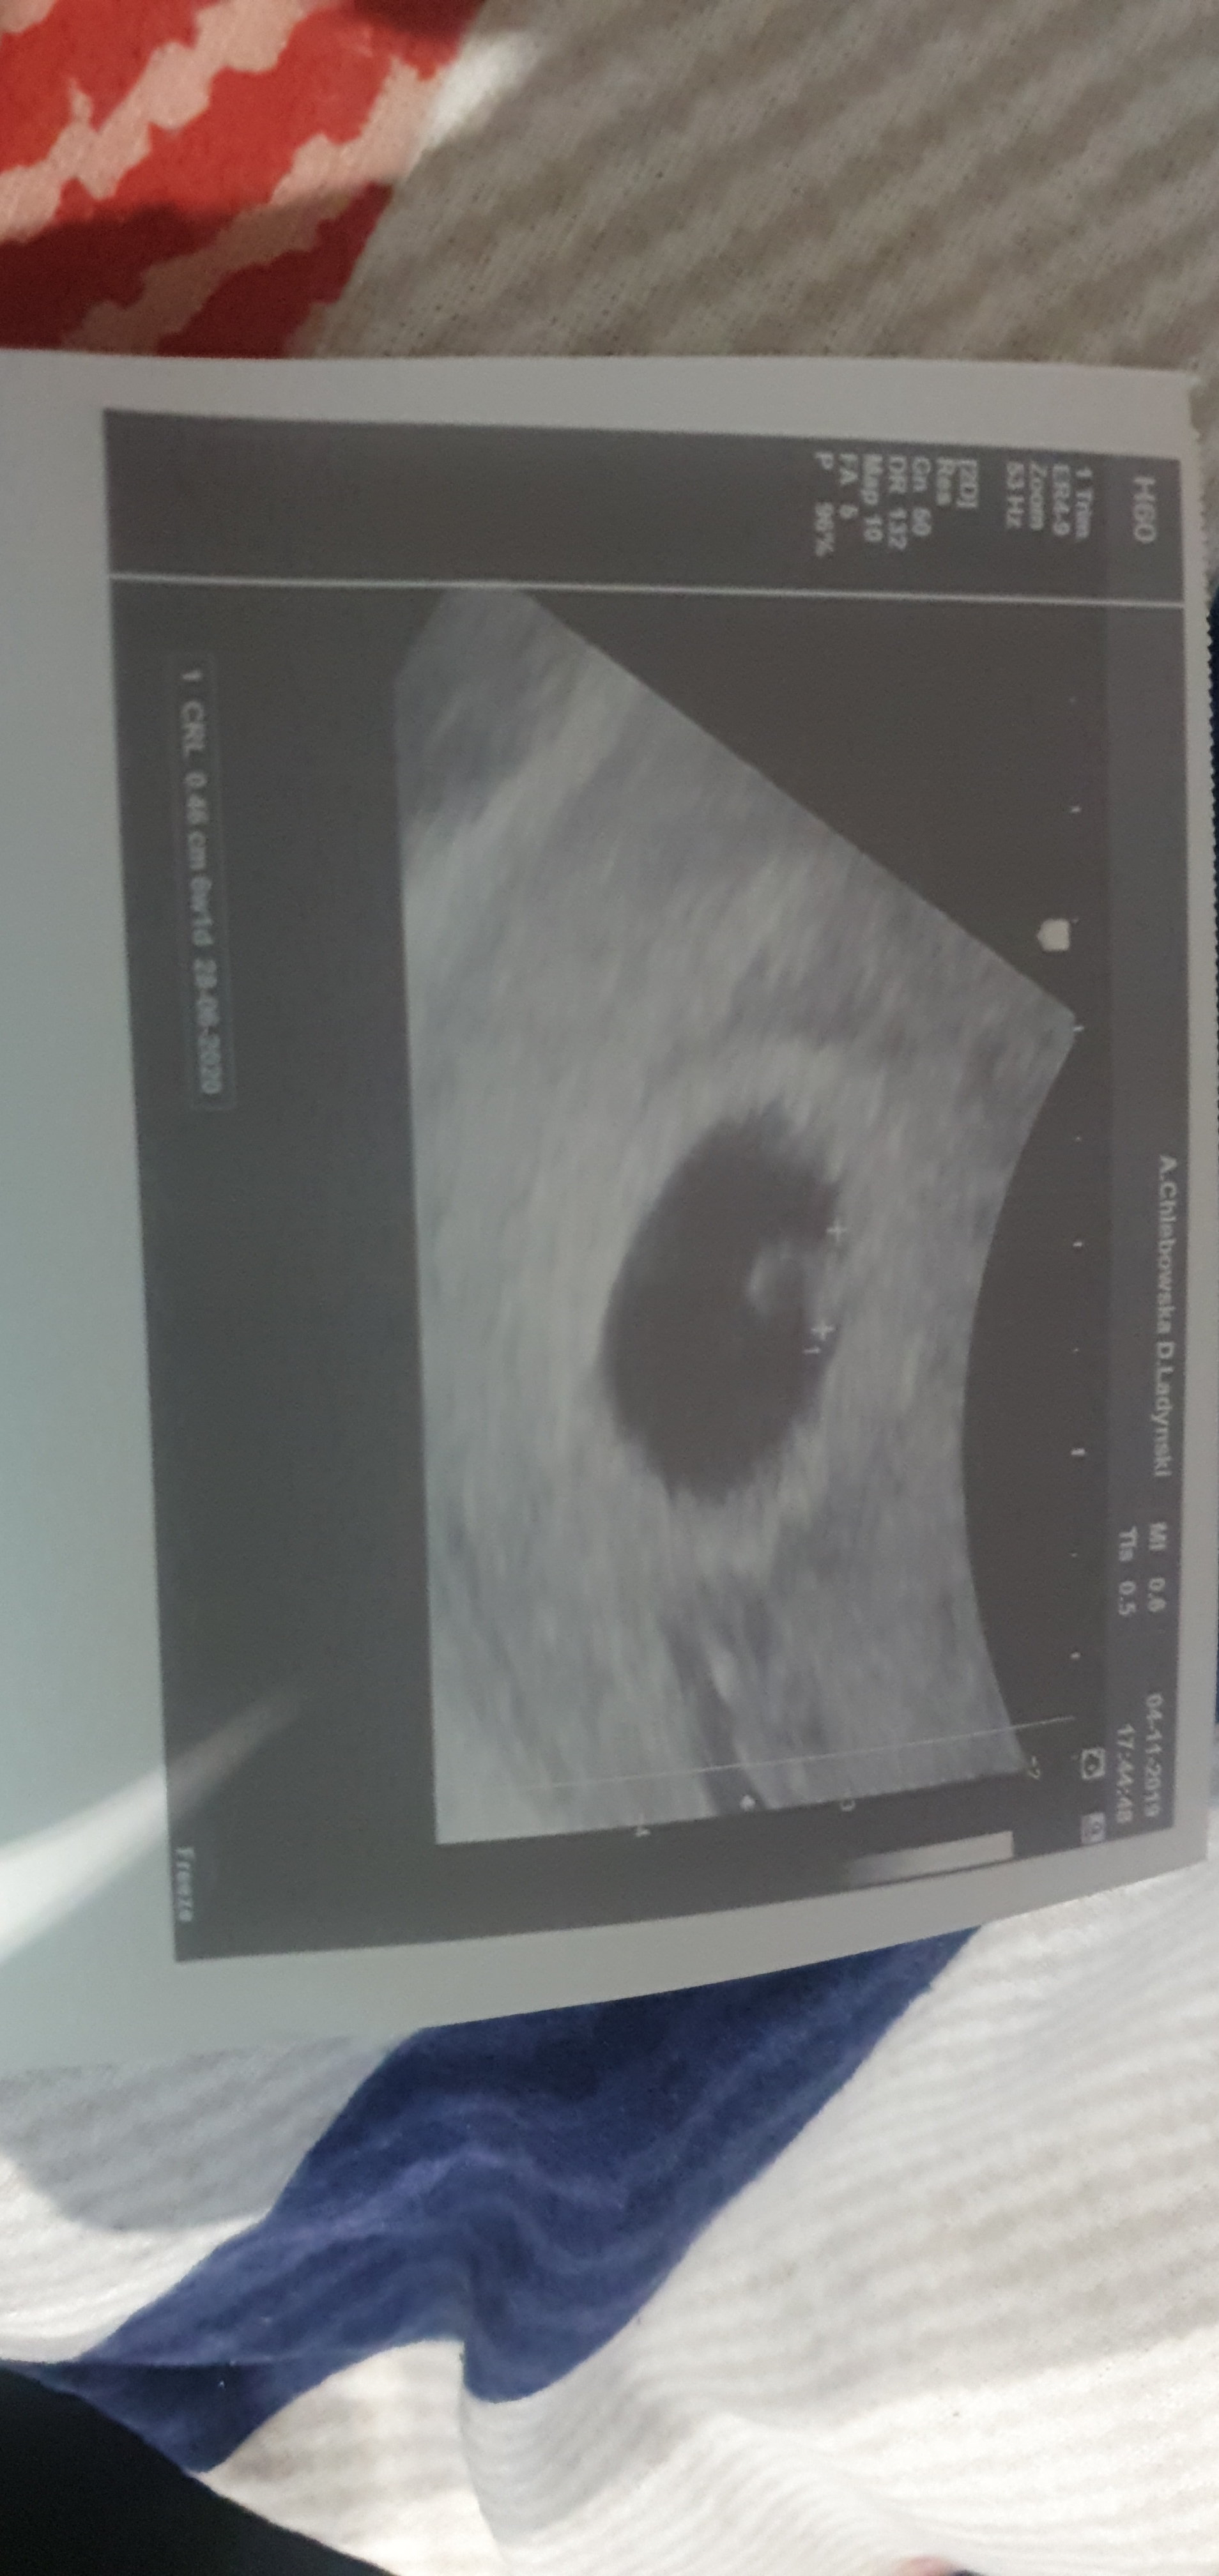

Super....Ja po wizycie. 2 cm czlowieka. Termin ok 13 czerwca. Generalnie wszystko ok i za miesiac mam sie umowic na prenatalne.